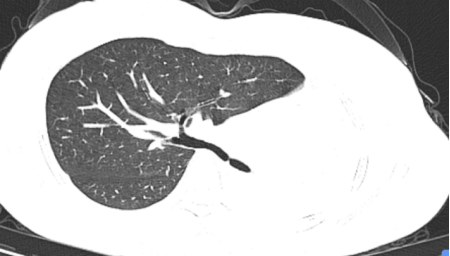

这不看不知道,一看吓一跳!胸部CT结果显示左肺完全不张,病人及家属emo了,“肺没了?”难道从此就要开启“半肺人”的下半生了吗?怎么办?

镜到之处,目之所及:左主支气管开口呈瘢痕样狭窄,远端支气管闭塞。难怪CT上只看到一边的肺,现在真相大白了!患者目前左肺开口处被肺瘢痕完全封堵,形同虚设,只有右肺可以用。